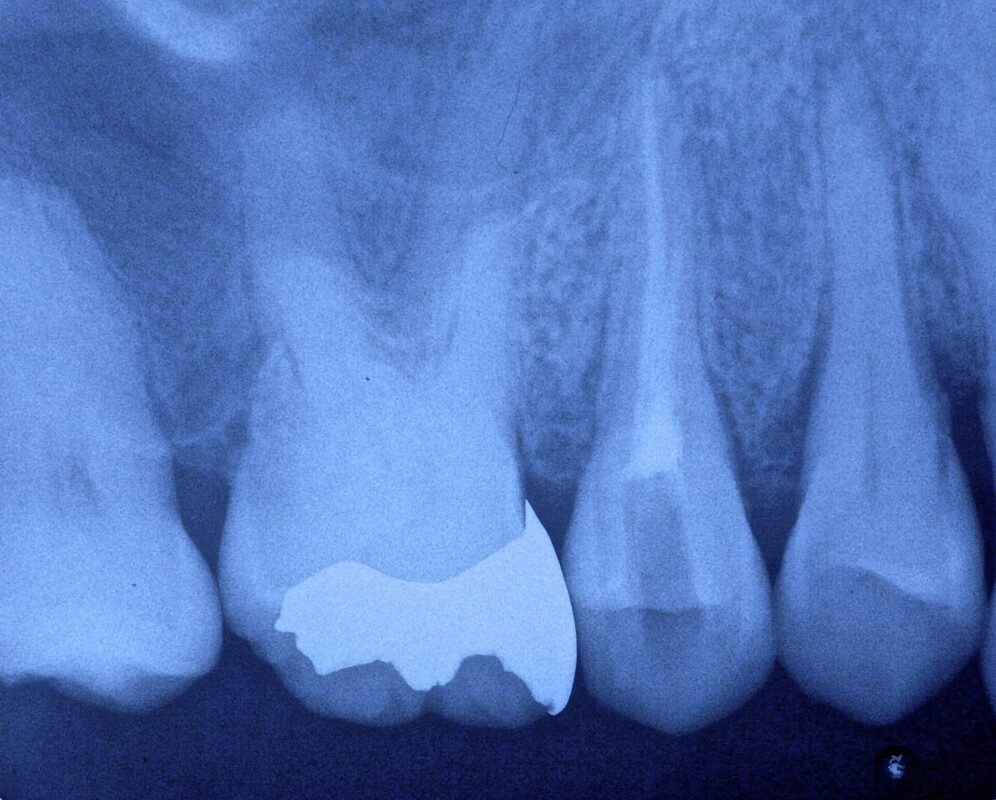

歯根破折歯の治療

痛いとの主訴で来院されました。

真横に割れています。

根管充填後